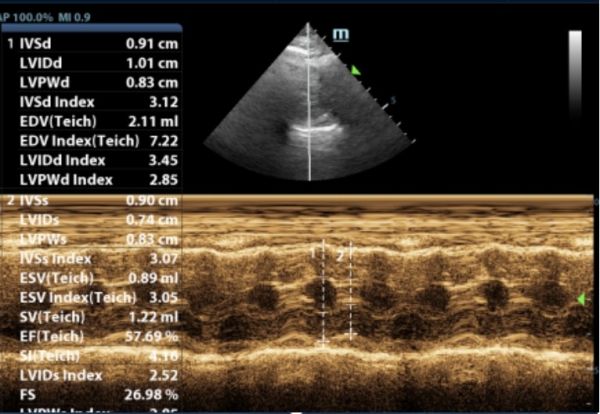

此前,6岁的猫咪因抽搐呕吐,后腿无力就诊,经查后发现左心室心肌及室间隔厚度增加,主动脉和二尖瓣均存在反流,诊断为肥厚型心肌病。口服利尿剂和抗血栓药物,一周后精神好转,再无出现抽搐、呕吐、后腿无力等现象。